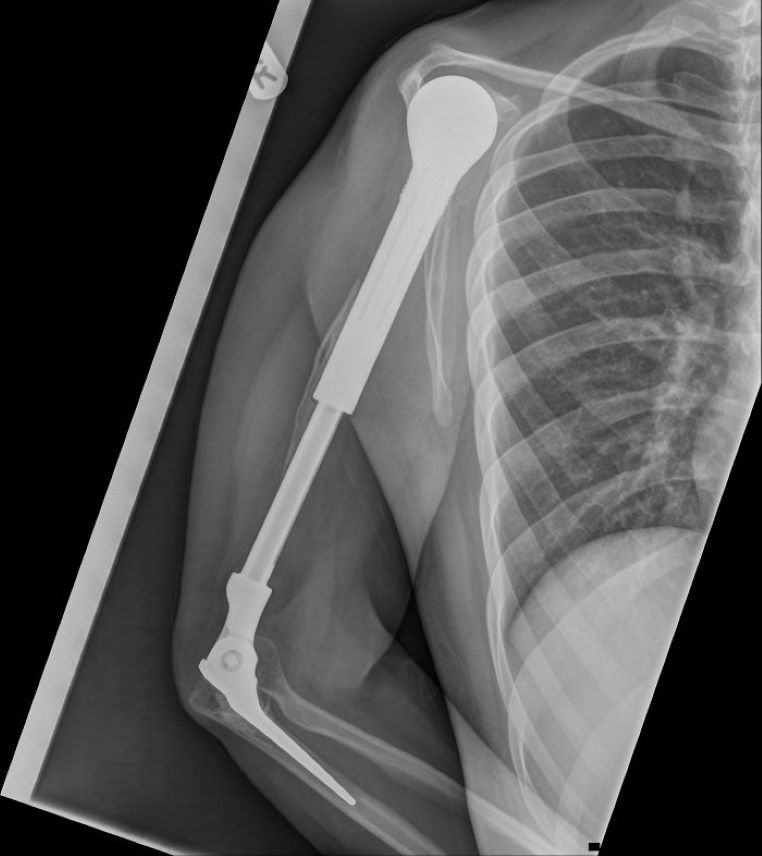

La radio d’un bras en métal

galerie-rayon-x-bras-métal